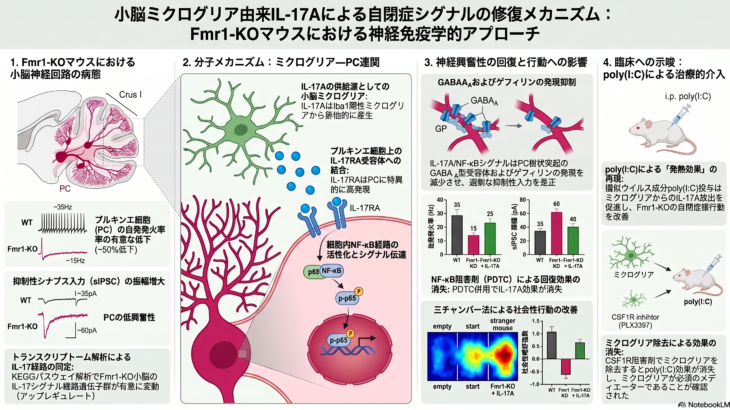

週末は台風と地震で落ち着かない時間を過ごしました。ラボセミナーでは、医療科学類4年生が論文紹介を行いました。大学院生はインターンのエントリーシートの作成や講義、レポート課題などで忙しいようです。夏の大学院入試や次の実習が 続きを読む

妊娠期の胎内環境と精神疾患および大脳皮質領野形成に関する研究を一緒に行ってくれる学生・研究員を募集しています。筑波大学の学類生でしたら、先導的研究者体験プログラム(ARE)による研究室参加も可能です。大学院は、フロンティ 続きを読む